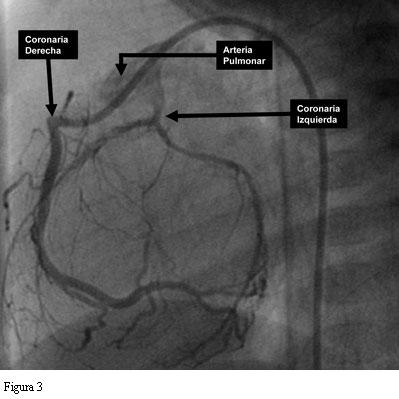

En base a la sospecha clínica basada en el ECG se indicó y realizó un cateterismo cardíaco. En la figura 2 se muestra una foto tardía de la ventriculografía izquierda luego de una inyección prolongada. Se observa el ventrículo izquierdo francamente dilatado, una aorta normal y la arteria coronaria derecha que se origina normalmente en la misma. Afuera y debajo del arco aórtico se observa un vaso que llega hasta la arteria pulmonar. Es la arteria coronaria izquierda que, con su flujo invertido, drena y tiñe débilmente la arteria pulmonar. En la figura 3 se muestra una coronariografía derecha selectiva en proyección oblicua izquierda. Allí se ve aun más claramente la arteria coronaria izquierda drenando en la arteria pulmonar.